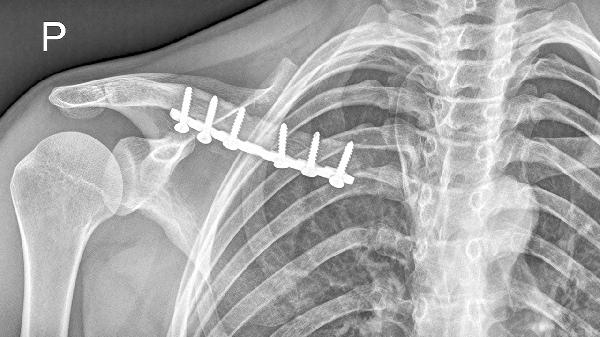

术后1周、4周、12周需复查X线观察骨痂形成情况。医生将根据愈合进度调整固定方式,部分患者需逐步过渡到肩关节吊带。若复查发现内固定松动或延迟愈合,可能需二次手术干预。